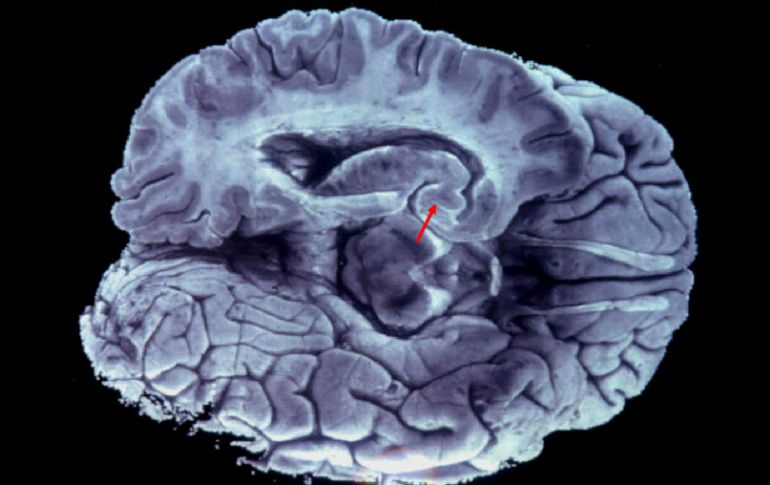

La amígdala es la parte encargada de procesar el miedo y la mayor parte de las emociones de carga negativa como la ira. EFE / ARCHIVO

La amígdala es una de las partes más profundas del cerebro, que, desde el punto de vista evolutivo cuenta con estructuras subcorticales antiguas, como, además de la amígdala, el hipocampo, y otras posteriores como la corteza, la parte externa que cubre los dos hemisferios.

Esta parte del cerebro es la encargada de procesar el miedo y la mayor parte de las emociones de carga negativa como la ira.